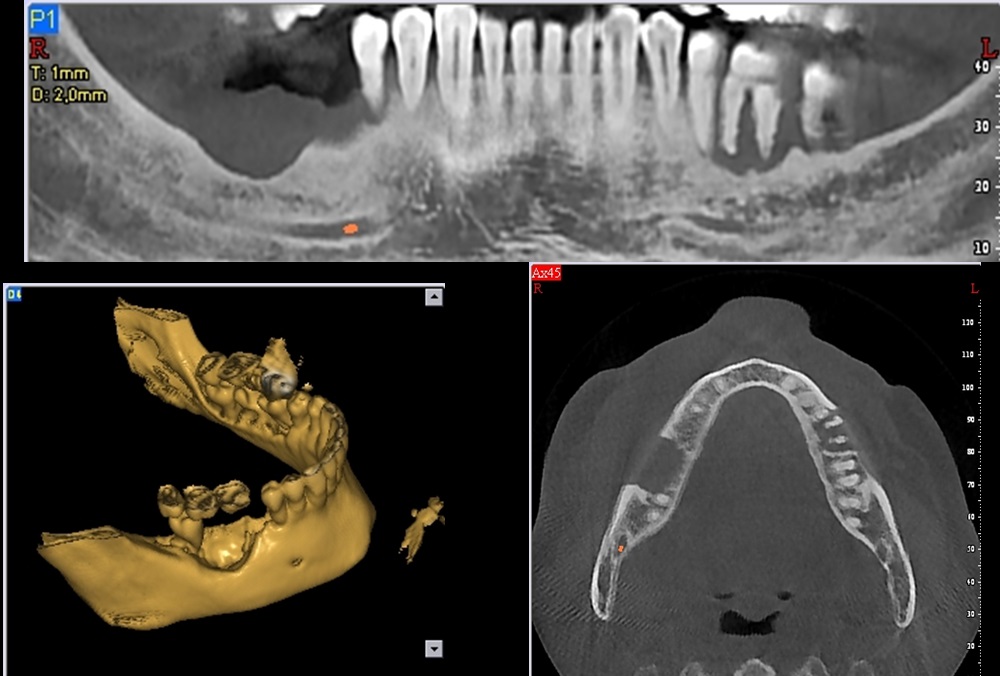

- The radiographic findings depend on the degree of infiltration. Computed tomography is necessary to accurately determine bone invasion and destruction.

- Radiographically an ill defined, osteolytic radiolucency, is observed which initiates as peripheral bone erosion.